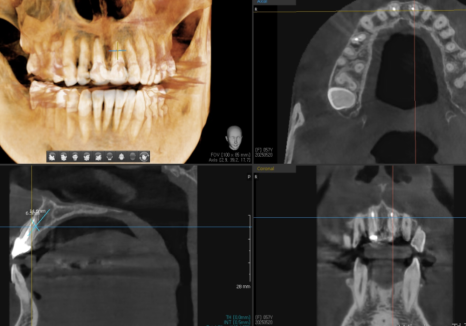

CT로 정확한 위치

확인 후 식립

잇몸 까매짐 원인,증상,치료 방법

250520

그래서 저는 식립 전 CT로

정밀하게 계획을 세우고

식립 후에도 촬영해서 의도한 대로

정확하게 들어갔는지 한 번 더 확인합니다.